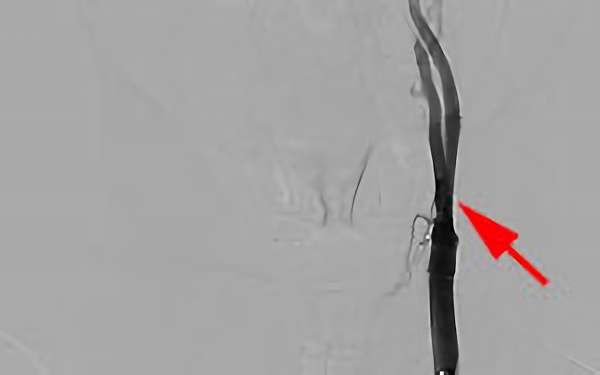

378

'19年1月30日

左内頚動脈狭窄症

70代

大阪府の病院

'19年1月